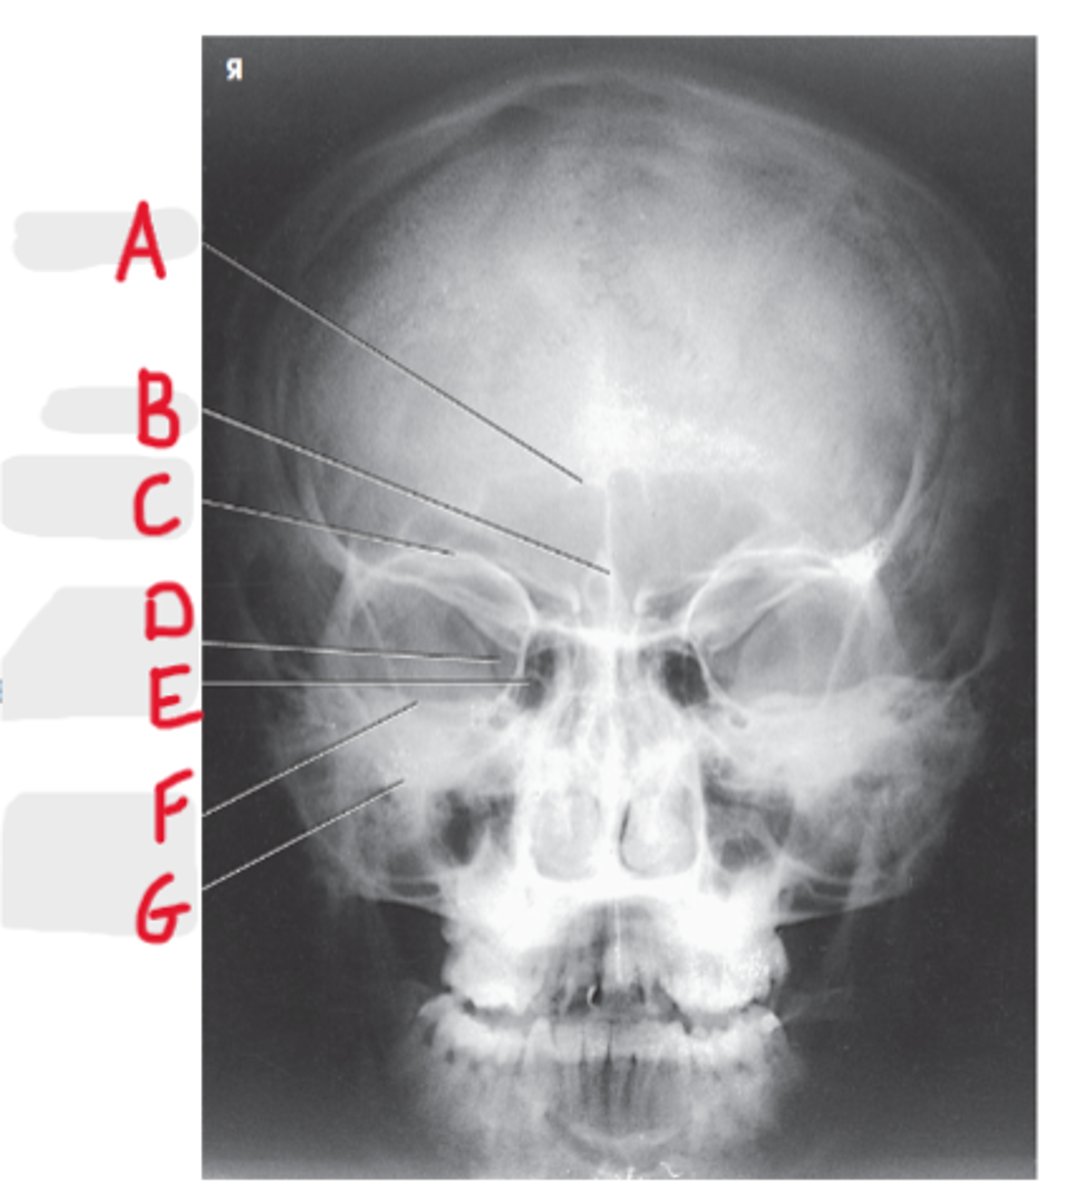

Frontal Sinuses

A

Ethmoid Sinuses

B

Maxillary Sinus

C

Petrous ridge

D

Mastoid air cells

E

PA axial (Caldwell Method)

What projection is this?

CR exits the nasion & 15 degree caudal angle

What is the CR for PA axial (Caldwell Method)?

OML perpendicular to IR

What line should be perpendicular to the IR for a PA axial (Caldwell Method)?

Interpupillary line (IPL)

What line is parallel to the IR for a PA axial (Caldwell Method)?

Frontal and Ethmoid

What sinuses are clearly demonstrated on the PA axial (Caldwell Method)?

Lower 1/3 of orbits

Where are the petrous ridges located in a PA axial (Caldwell Method) radiograph?